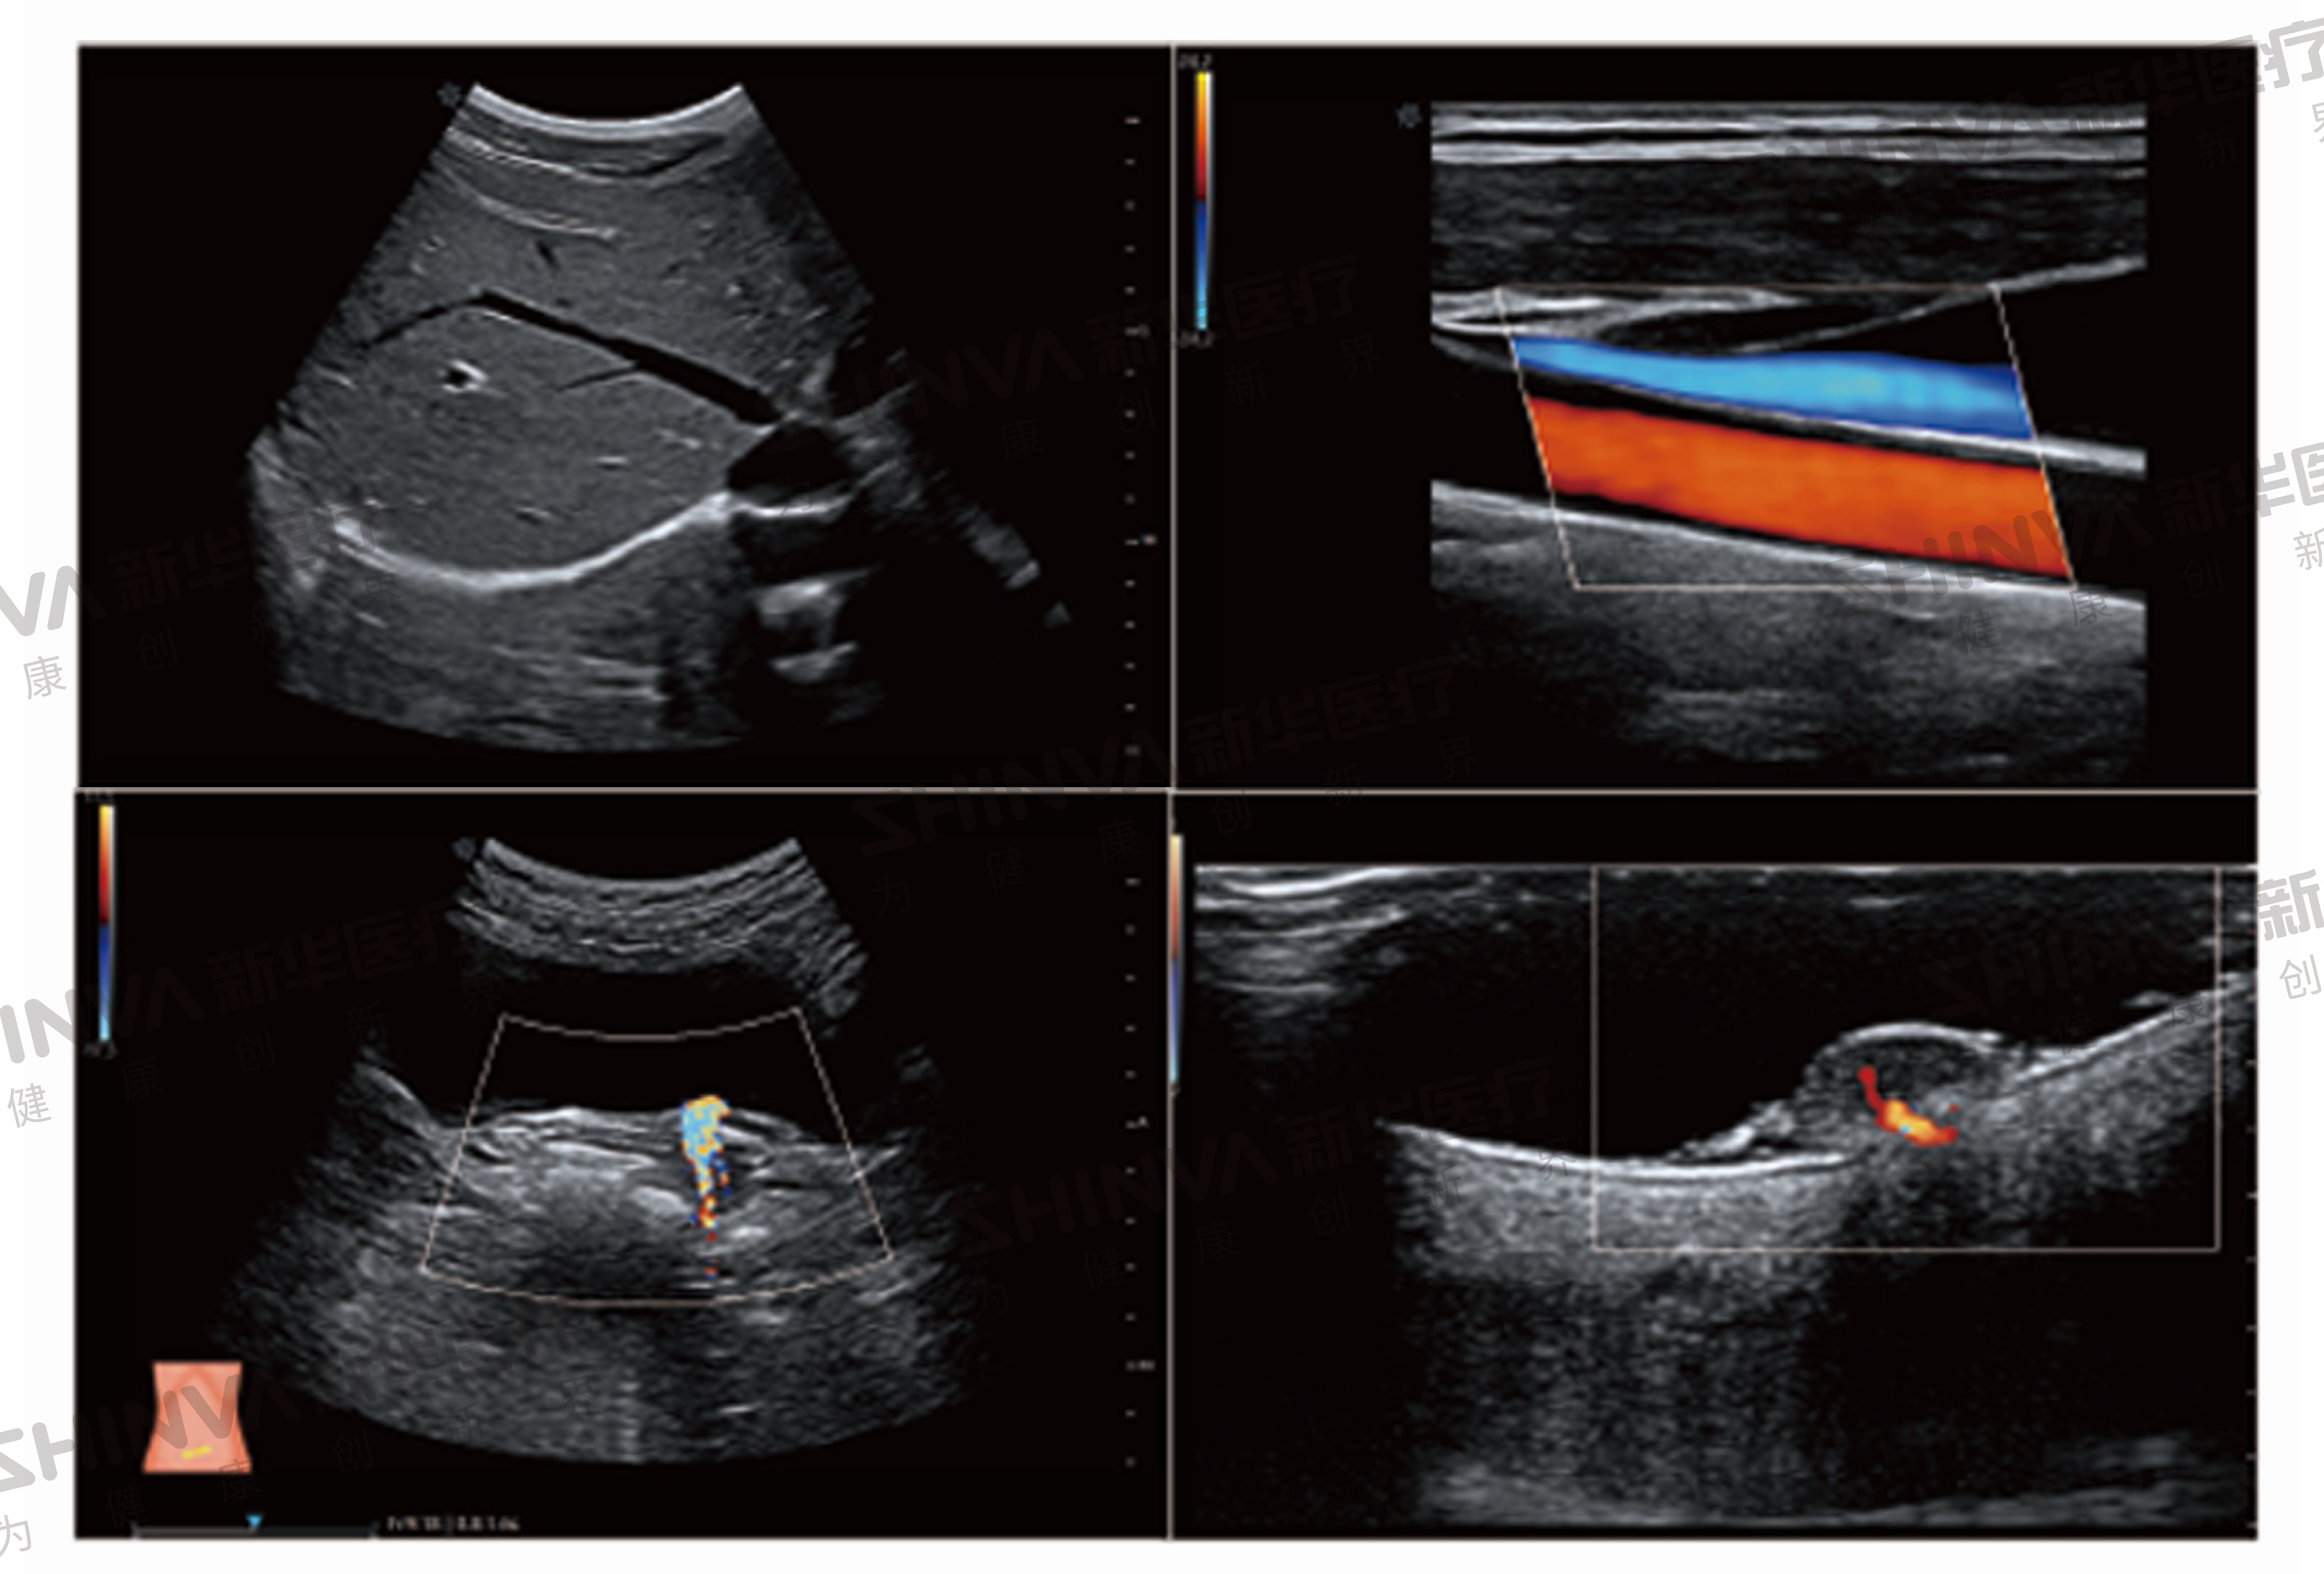

系統搭載全新單晶體探頭及高端成像技術,輕松獲得更高質量的圖像。系統采用最先進的發射接收技術,保證圖像整場均一性的同時,大幅提升圖像的分辨率、穿透力和高端應用性能,助力臨床疑難病例的診斷教學。

智能應用:智能產科分析、NT自動測量、甲狀腺實時智能分析、乳腺實智能分析、小兒髖關節半自動測量、心功能自動分析、智能血管應用成像、智能多普勒